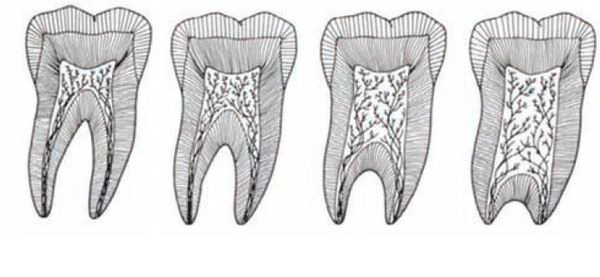

Na przykład taurodontyzm – czyli tzw. „byczy ząb” – to stan, w którym ząb jest powiększony i wydłużony, a jego komora miazgi (środkowa część zęba) jest znacznie rozciągnięta.

Zjawisko to wynika z mutacji chromosomowych, prowadzących do nieprawidłowego rozwoju twardych tkanek zęba.

Nietypowy kształt, kolor i struktura zębów mogą wynikać z zaburzeń ogólnoustrojowych, czynników środowiskowych lub działania substancji chemicznych w kluczowych etapach rozwoju zębów. Jedną z częstych przyczyn deformacji korony jest niedoczynność tarczycy (hypotyreoza) – choroba, w której gruczoł tarczowy produkuje zbyt mało hormonów. Skutkuje to pogorszeniem stanu szkliwa: pojawiają się pęknięcia, przebarwienia (żółtoszare lub zielonkawe odcienie), a zęby szybciej się ścierają i stają się podatne na próchnicę, erozję oraz martwicę twardych tkanek. U dzieci z niedoczynnością tarczycy proces ząbkowania jest wyraźnie opóźniony – zęby mleczne mogą wyrzynać się kilka lat później, a zęby stałe nawet 3–4 lata po typowym czasie. Badania pokazują, że aż 61,1% dzieci z hypotyreozą ma anomalia zębowe i szczękowo-twarzowe. Przyczyną tych zmian jest niedobór hormonów tarczycy zawierających jod, które regulują skład śliny, aktywność enzymów i mikrokrążenie w tkankach jamy ustnej.

Niektóre czynniki chemiczne lub biologiczne działające na płód mogą zaburzać mineralizację i rozwój twardych tkanek, prowadząc do hipoplazji szkliwa – czyli częściowego lub całkowitego braku szkliwa. Taka wada objawia się matową, porowatą powierzchnią, ubytkami i zwiększoną wrażliwością zębów.